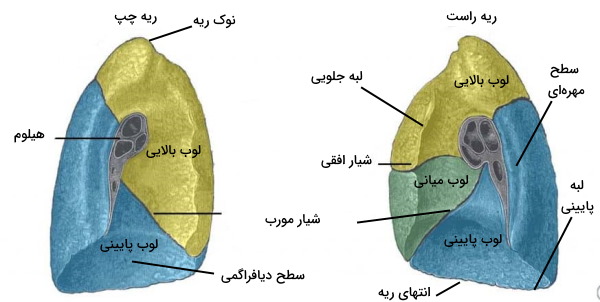

آناتومی ریه

ریهها اندامهایی مخروطی شکل دو طرف استخوان جناغ و چسبیده به نایژه اول هستند. هر ریه از یک بخش «نوک» (Apex)، «قاعده» (Base)، سه لبه و سه سطح تشکیل شده است. نوک بخش بلایی و مخروطی ریه است که بالاتر از دنده ۱ و پایین گردن قرار دارد. پایه بخش انتهایی ریه است که بالای دیافراگرام قرار میگیرد. سطح دندهای پشت استخوان دندهها، سطح دیافراگمی بالای ماهیچه دیافراگم و سطح میانی دو طرف استخوان جناغ قرار دارد. لبه جلویی نزدیک استخوان جناغ و دندهها قرار دارد. فررفتگی (Cardiac Notch) لبه جلویی در ریه چپ محل قرار گرفتن قلب است. لبه پایینی انتهای ریه را از سطح دندهای و میانی (مدیاستال) جدا میکند و لبه پشتی سطح دندهای و میانی را در پشت ریه از هم جدا میکند.

هر ریه از بخشهای کوچکتری به نام لوب تشکیل شده است که بافت عصبی، خونی و مسیرهای تنفسی متفاوتی دارند.

- لوبهای ریه راست: ریه راست از سه لوب بالایی، میانی و پایینی تشکیل شده است که شیارهای افقی و مورب آنها را از هم جدا میکند. شیار مورب لبه پایینی ریه را به لبه پشتی ریه وصل میکند و شیار افقی همسطح دنده چهار از جناغ سمت شیار مورب حرکت میکند.

- لوبهای ریه چپ: ریه چپ از دو لوب بالایی و پایینی تشکیل شده است که بهوسیله شیار مورب ( لبه پایینی به لبه پشتی) از هم جدا میشوند.